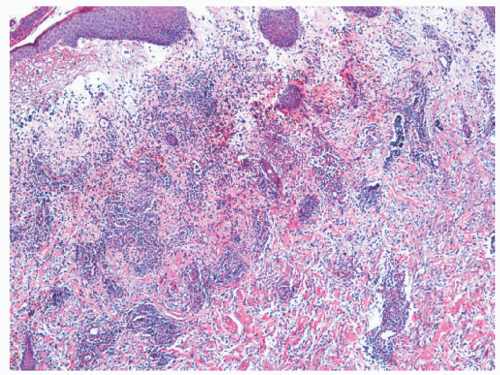

Histologic Findings

Microscopic findings include dense neutrophilic infiltrates in the deep dermis, subcutaneous tissue, and underlying fascia (Figures 17-14 and 17-15). Tissue necrosis and vascular thrombosis are commonly seen, and Weedon defines NF as a form of septic vasculitis.21 Bacteria can be present in sheets, and they may be seen with Hematoxylin and eosin (H&E) stain.